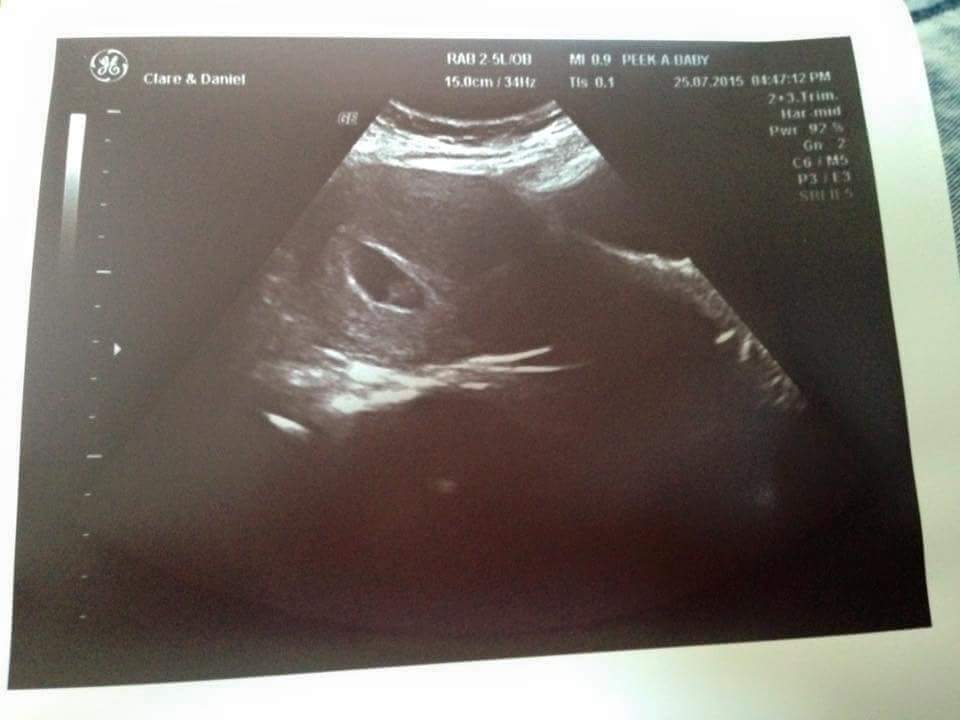

Hi guys had an early reasurance scan yesterday I was exactly 8 weeks can anyone guess the gender of my baby using the ramzi method it was an abdominal ultrasound TIA XXXAttachment 26435

Thanks for your reply She said the yolk sac was attatched to left of my uterus xx

Based on ramzi, if this was transvaginal, looks like girl